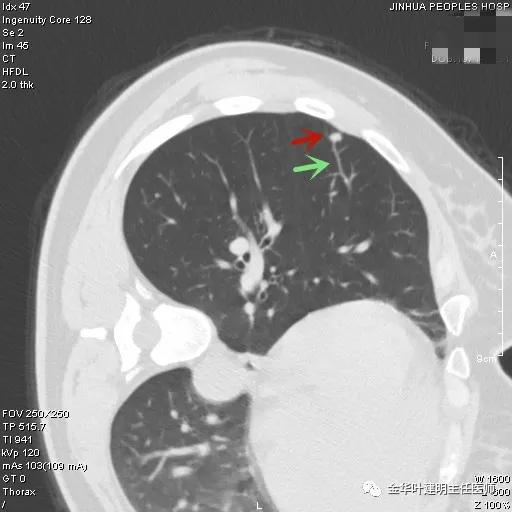

上图示浸润性腺癌典型表现。实性结节,有细毛刺征,有血管进入病灶,部分地方有浅分叶。